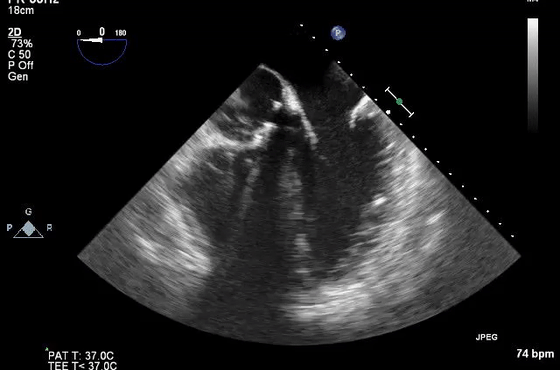

10、经食管超声图像伪像

虽然上面介绍的主要集中在常规经胸超声心动图,但上述伪像也经常在经食管超声心动图中遇到。图10显示了经食管超声心动图中一些常见的伪像。在这方面最相关的临床情况是(1)排除LAA中的血栓(图10E和10F)和(2)排除主动脉夹层(图10G和10H)。

图10经食管图像伪影。

(D)疑似两个平行的主动脉(Ao)的镜像伪影(星号)。注意血流也产生镜像伪像(视频17)。

(E)左心耳疑似血栓的混响伪影。从多个角度(见图F)进行分析证实存在华法林嵴的混响(星号),而不是真正的血栓(视频18-19)。

(G)在升主动脉(视频20)中延伸的钙化窦管连接(箭头)的旁瓣伪影(箭头)不应被误解为夹层。

(H)同样,升主动脉中的回声可能会被误解为夹层。